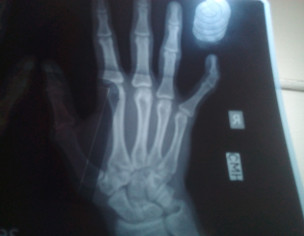

My pinky fingers of both hands are wedge shaped

it's a bony problem.

if it's hindering your function, surgery will be required to correct the deformity.

If your hand functions well then there is no need for surgical intervention. May be you are concerned about deformity and if so then you should consult in person as hand problems need physical examination for assessment and management.